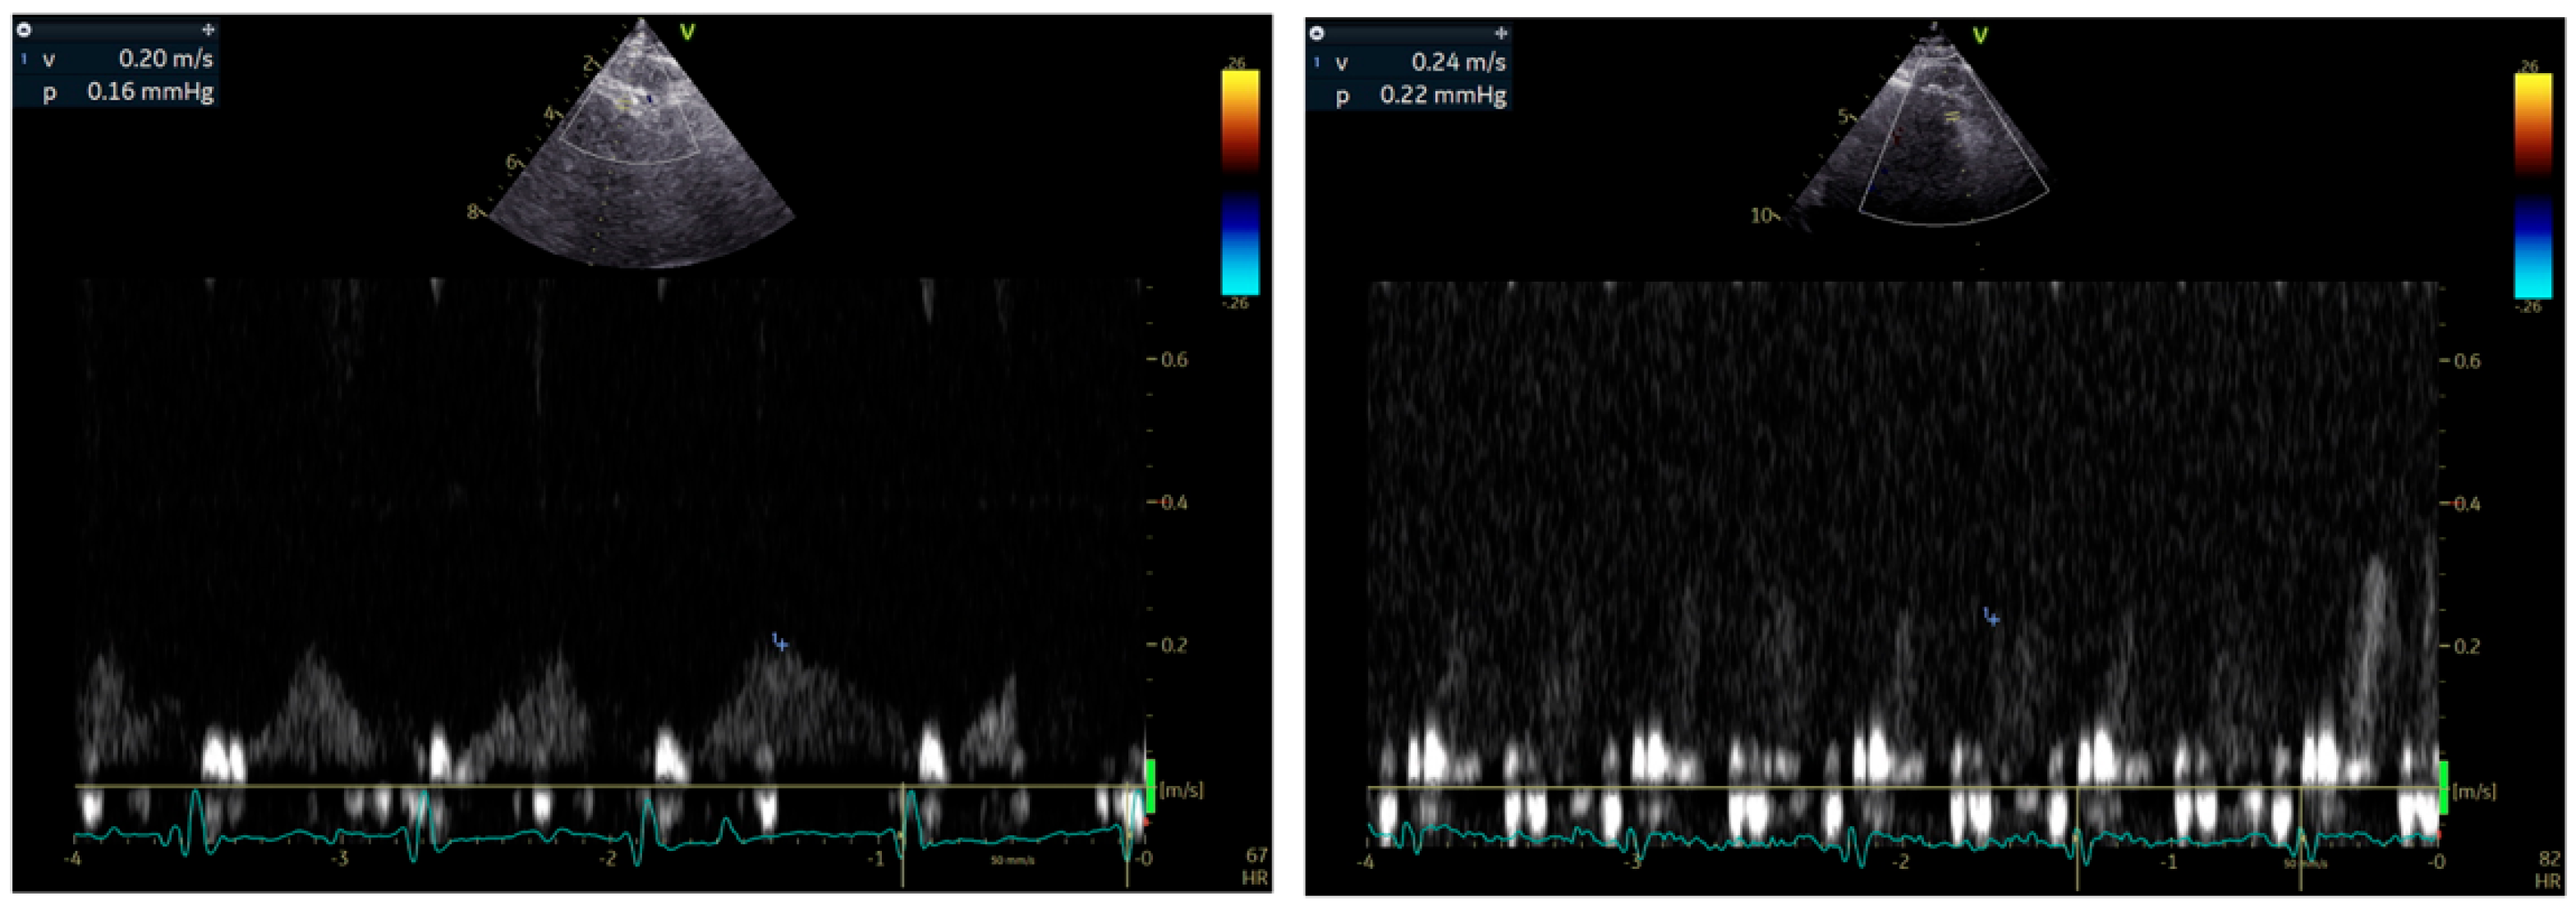

Stress echocardiography (SE) remains a first-line technique for the diagnosis of significant CAD affecting epicardial coronary arteries. Wall motion abnormalities are usually not detected in patients with CMVD undergoing SE with dobutamine or exercise as stressors. Some operators have reported isolated hypokinesia of the apical segment of the interventricular septum, but this has not been established. Using the Doppler method and a modified apical view (between 2 and 3 chamber), CFR can be measured during SE as an index of either absolute coronary flow in the LAD or microvascular circulation patency [42] (Figure 2). CFR is calculated as the ratio of baseline to hyperemic coronary flow velocity, measured by pulsed-wave Doppler during diastole, with vasodilators like dipyridamole or adenosine inducing hyperemia. This is a widely used and easily accessible technique, which unfortunately cannot distinguish macrovascular from microvascular dysfunction. In patients with MINOCA only after the exclusion of significant stenosis in LAD, a low CFR (<2) indicates CMVD with impaired ability of the vasculature to dilate adequately and meet metabolic demands during hyperemia [57,69,70]. However, CFR is not directly associated with fractional flow reserve (FFR) due to its dependence on microvascular resistance [37]. This discrepancy explains why CFR and FFR are often discordant in approximately 30% of patients with intermediate coronary artery stenoses of the LAD [71]. Despite this, CFR complements FFR findings, offering additional insights into coronary microvascular physiology, especially when assessing the interplay between epicardial stenosis and microvascular function [37]. In daily clinical practice, the timing of applying SE after an AMI remains to be set.

Figure 2.

Representative example of CFR calculation using echocardiography.